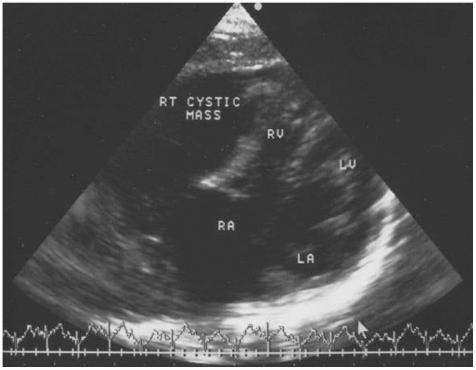

Right atrial aneurysm is an extremity rare congenital heart defect. We report a case which was diagnosed during the early fetal stage and operated on in a 2 week old neonate. Following median sternotomy, aneurysmectomy was performed under a cardiopulmonary bypass. Histopathological examination of the resected atiral tissue showed a lipotomatous degeneration and reduction of the muscular elements. There were no postoperative complications.